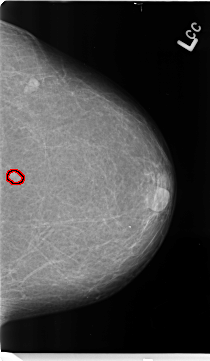

B_3153_1.LEFT_CC

LEFT_CC LINES 4688 PIXELS_PER_LINE 2720 BITS_PER_PIXEL 12 RESOLUTION 50 OVERLAY

FILE: B_3153_1.LEFT_CC.OVERLAY

TOTAL_ABNORMALITIES 1

ABNORMALITY 1

LESION_TYPE MASS SHAPE IRREGULAR MARGINS ILL_DEFINED

ASSESSMENT 4

SUBTLETY 4

PATHOLOGY BENIGN

TOTAL_OUTLINES 1

BOUNDARY